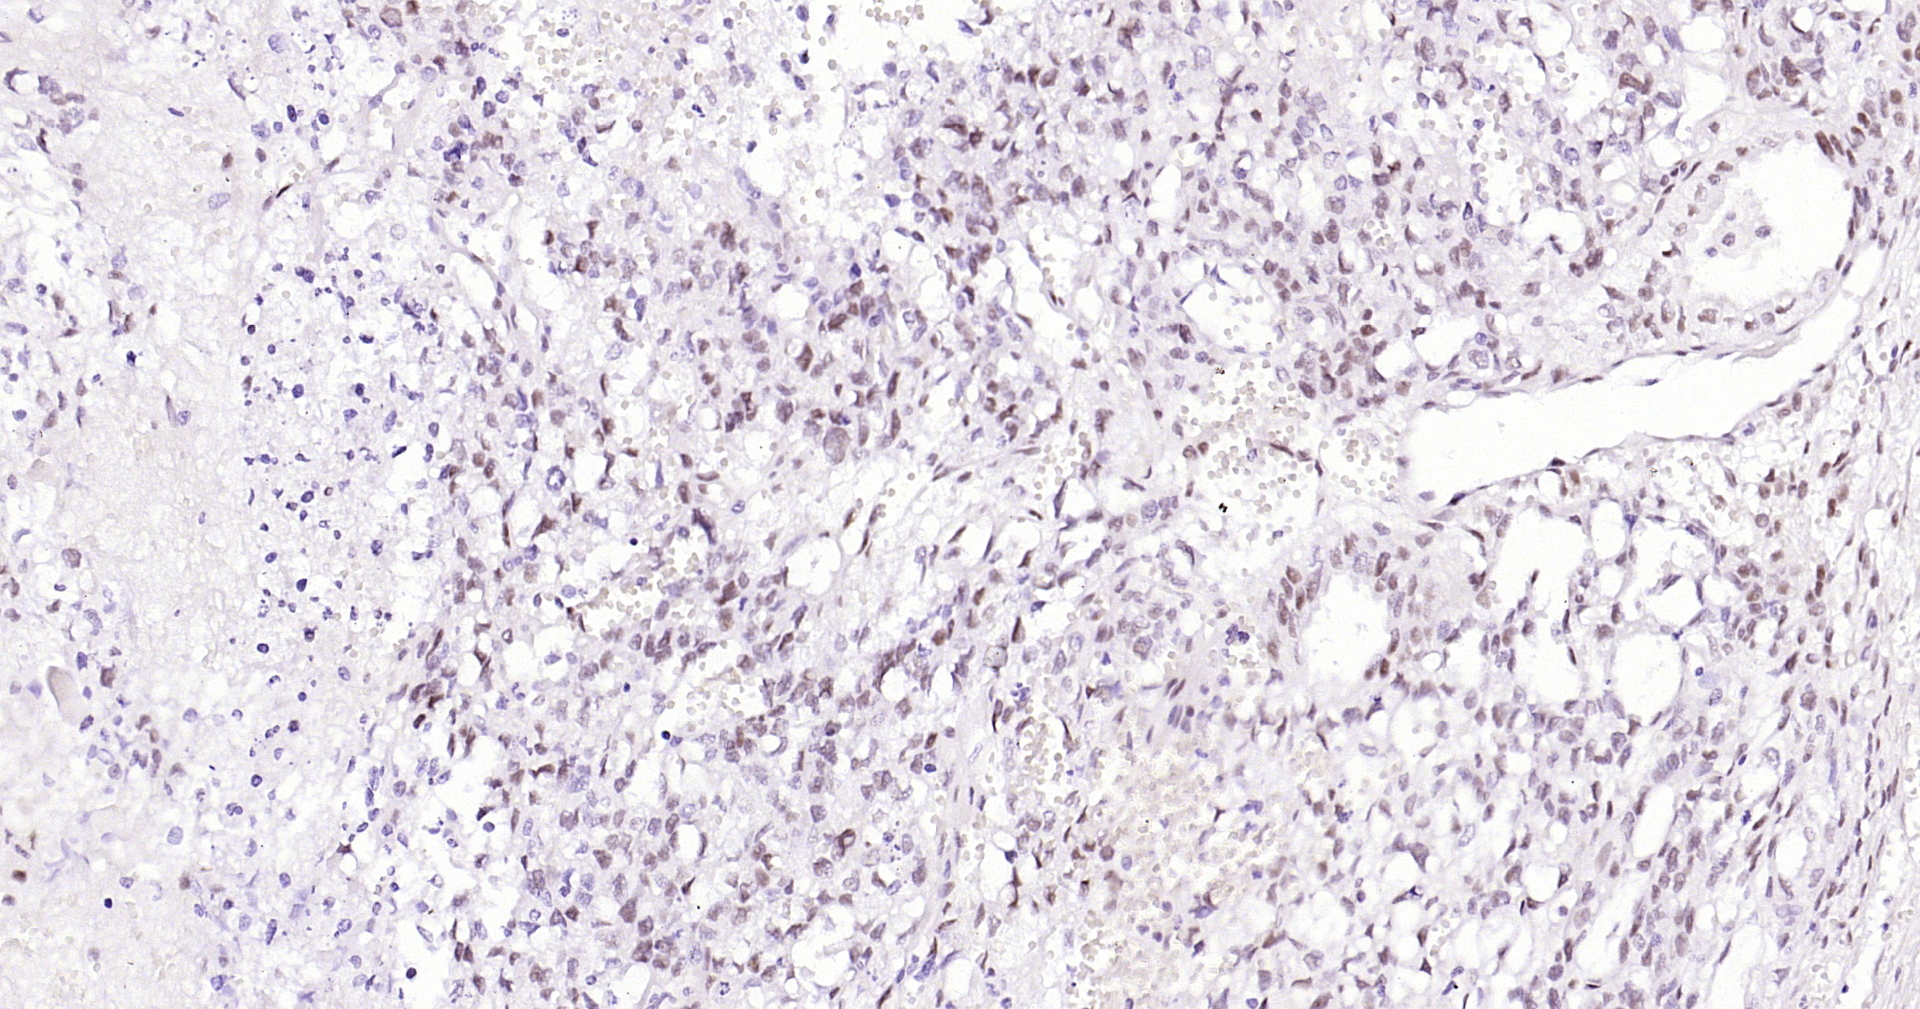

Progesterone Receptor

• IHC-P

Product Name Progesterone Receptor

Applications WB, FCM, IHC-P, IHC-F, IF(IHC-P), IF(ICC)

IHC-P IHC-P1:100-500